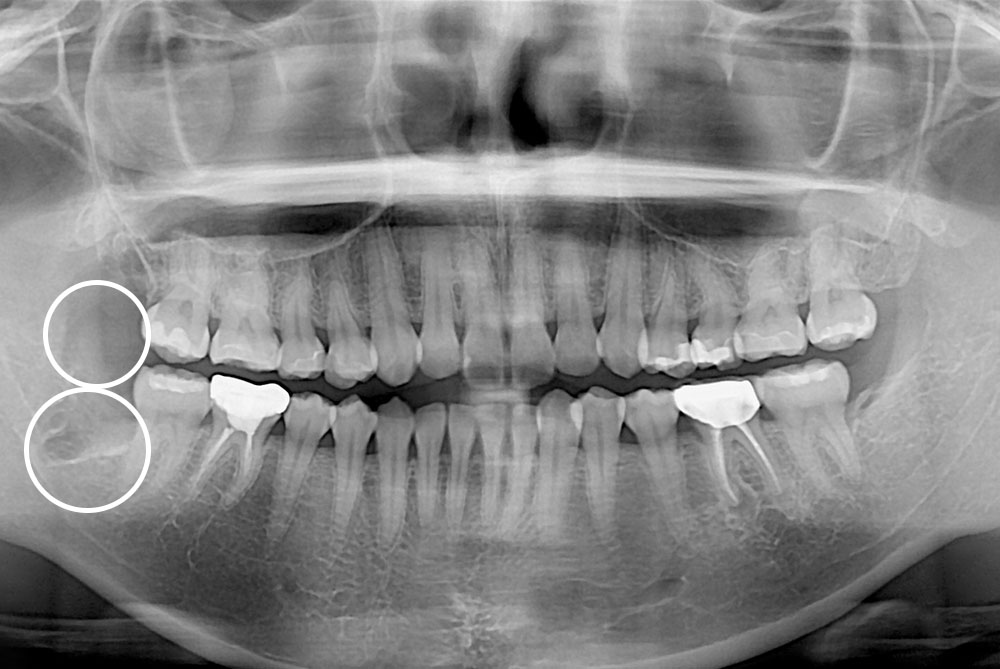

[사랑니] 매복 사랑니 발치

치료후 : 2019-07-24